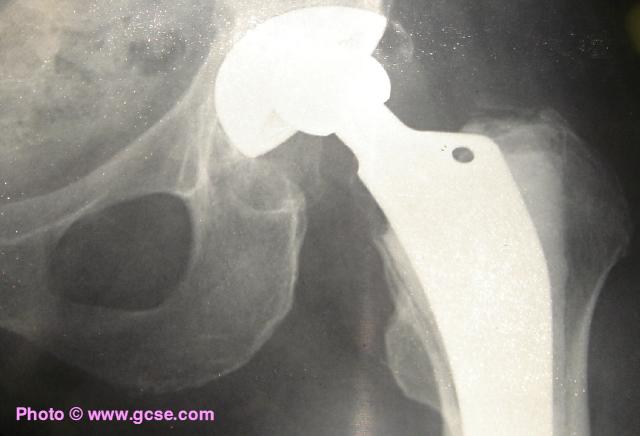

X-ray of healthy human hipX-ray of human hip showing replacement joint

X-rays are absorbed by bone, but pass almost perfectly through flesh. In the image above, the replacement hip joint is made of metal so blocks the passage of X-rays.